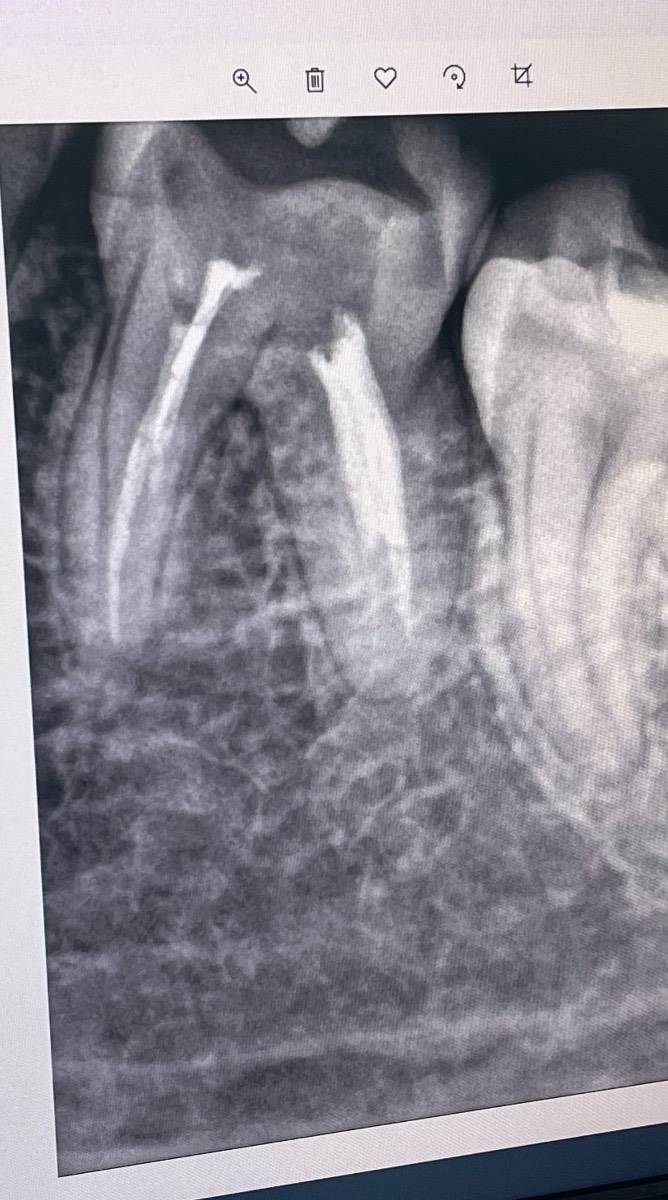

В конце прошлого года были депульпированы каналы в шестерке на нижней челюсти.

С января появилась боль при надкусывании и в целом я фоном всегда ощущаю эту область десны.

Первый снимок был сделан в январе, тогда мне сказали что ничего не видят критичного и отправили полоскать содой, пить антибиотик.

В феврале снова появились неприятные болезненные ощущения, снимок 2, другой доктор сказала, что по снимку есть небольшое воспаление десны у корня и такая ситуация  норма для «мертвого» зуба в холодное время года. Если не поможет нимесил (снял слегка ощущения, спустя пол недели вернулись) и повторный прием антибиотика, то его только удалять, так как по снимку проблем с каналами нет.

Снимки не очень информативны в таком варианте, но даже по ним есть вопросы и к пломбировке каналов и к состоянию зуба.